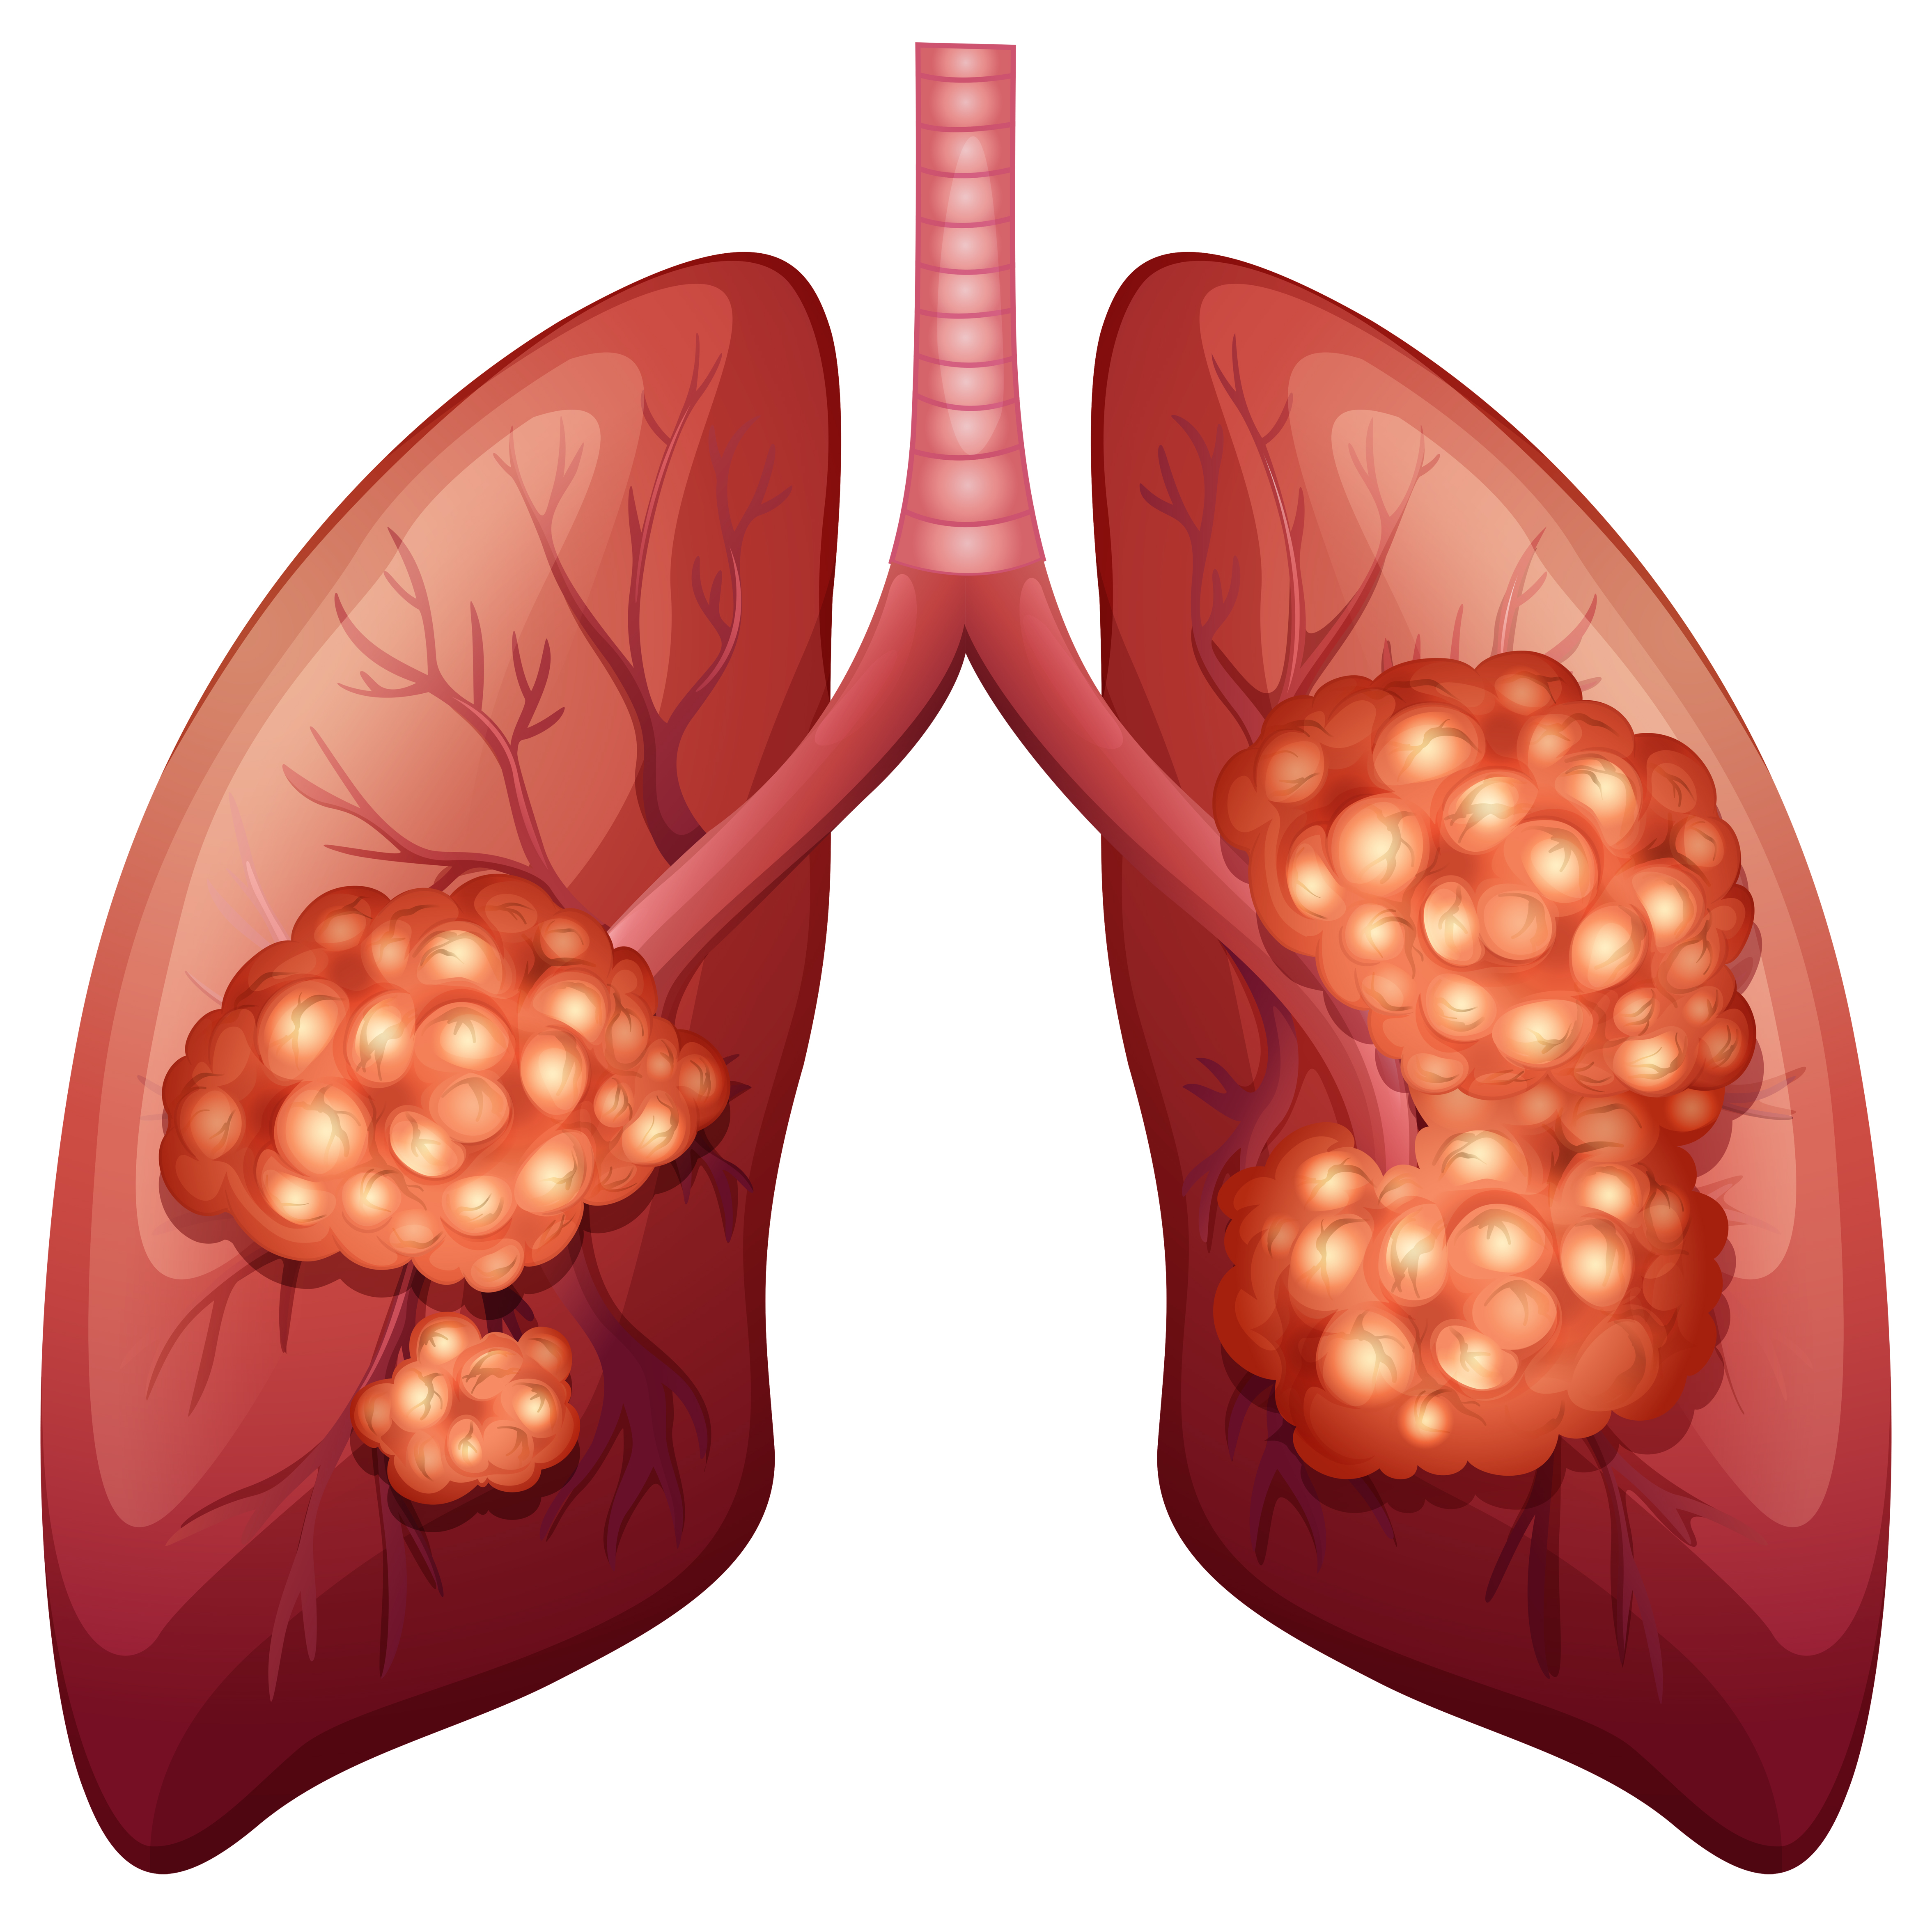

Лёгкие человека: Учебные картинки для детей